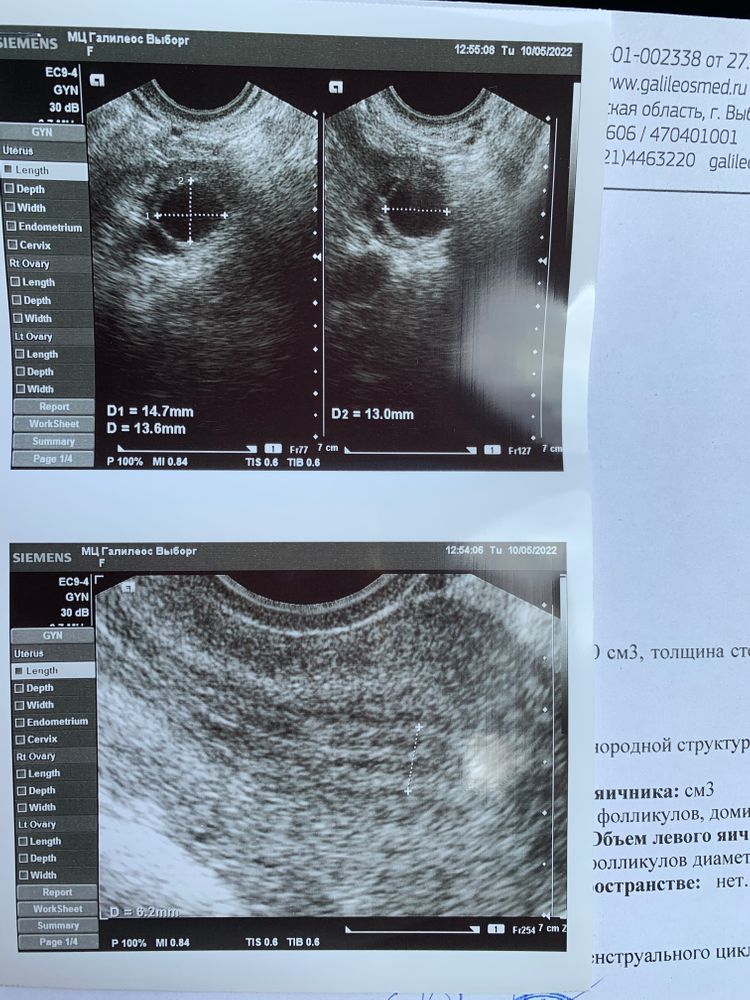

В этом месяце первый раз решила начать отслеживать овуляцию. Была сегодня на фолликулометрии на 12 день цикла. Цикл обычно 26-34 дня. Узист все время молчала и ничего не говорила. Спросила когда приходить следующий раз. Она ответила, чтобы я проконсультировалась со своим врачем (мой врач на приеме сказала прийти к ней через 6 месяцев). Вопрос собственно вот в чем. Когда примерно будет овуляция? Я так поняла, что с правой стороны тот который сейчас 13,8? Читала, что они в день растут на 1 мм и ломается, когда примерно 20 мм?